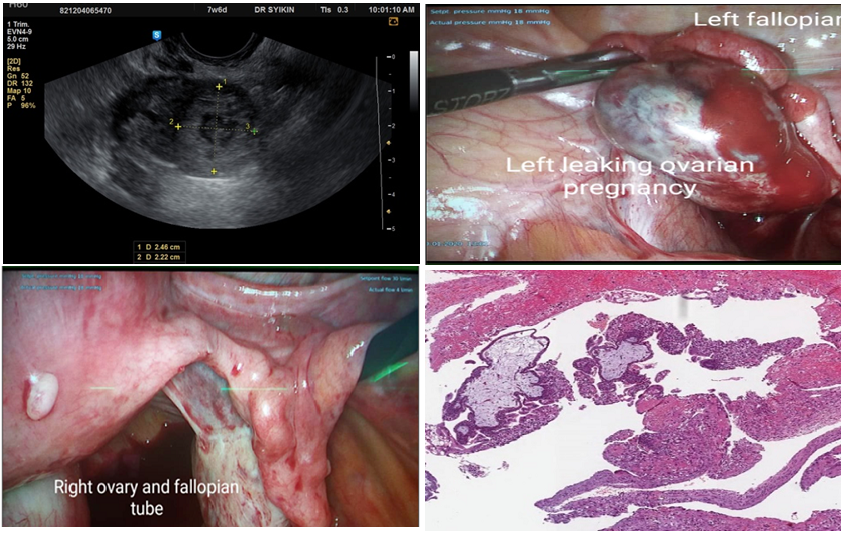

Open AccessCase Report

Ovarian Ectopic Gestation after Assisted Reproductive Technique with Intracytoplasmic Sperm Insemination

Muna Kh. Al Kubaisi, Md Azam Md Yusoff, Saad M. Al-Shibli, Nurul Jannah Ismail, Iza Emilia Md Ibrahim, Azha S. Azizan, Khairunisa Ahmad Affandi KA Affandi, Roszaman Ramli

International Journal of Innovative Research in Medical Science·March 5, 2022